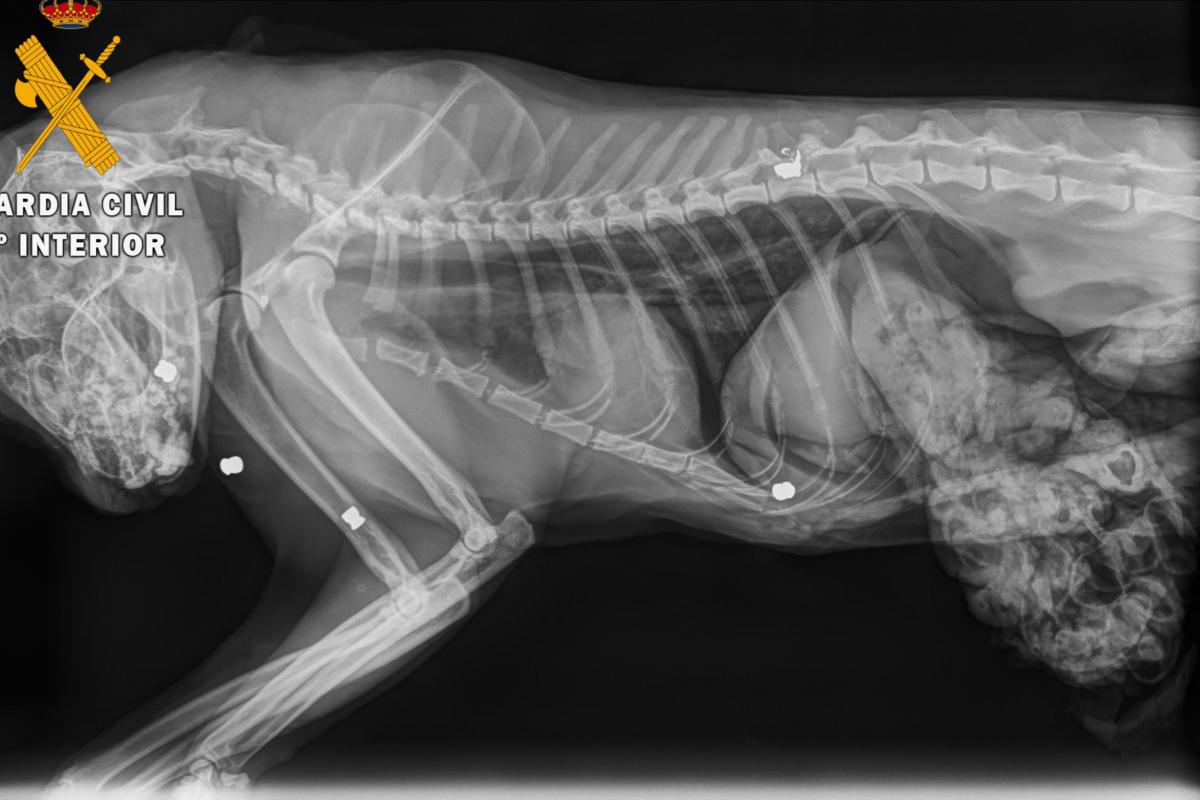

Al cuerpo del gato se le realizó una necropsia en una clínica veterinaria de Estella, donde se determinó que el animal había fallecido por el impacto de cinco perdigones. Se extrajo uno de los cinco proyectiles por si fuese necesario para un análisis.

Agentes del Servicio de Protección de la Naturaleza Seprona iniciaron una investigación en la zona, gracias a la cual se intervino una carabina de aire comprimido de calibre 4,5 mm a un vecino de la localidad, del que los agentes tenían sospechas de que pudiese ser el autor de los hechos.

El proyectil y el arma fueron remitidos al laboratorio de criminalística de la 10ª Zona de la Guardia Civil en La Rioja para la realización de los estudios balísticos. Finalmente, estos estudios establecieron que el proyectil encontrado en el cadáver del gato había sido disparado con el arma intervenida. Se procedió a investigar al dueño del arma como supuesto autor de un delito de maltrato de animal doméstico.